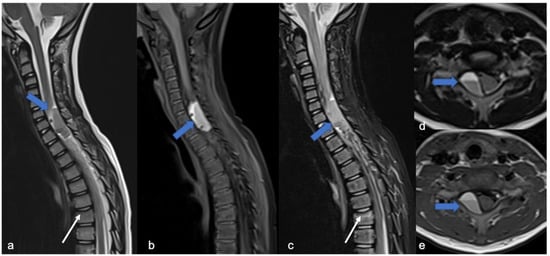

2.2. Diffuse Leptomeningeal Glioneuronal Tumor